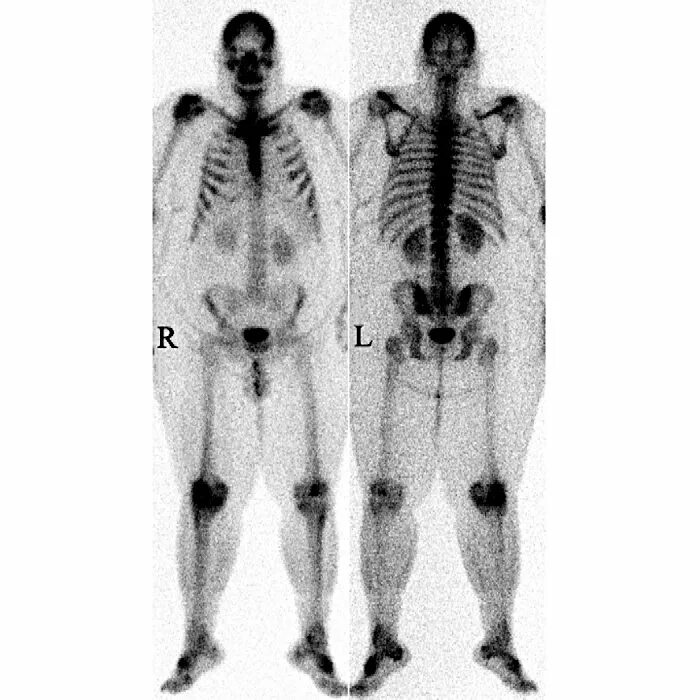

Метастазы скелета